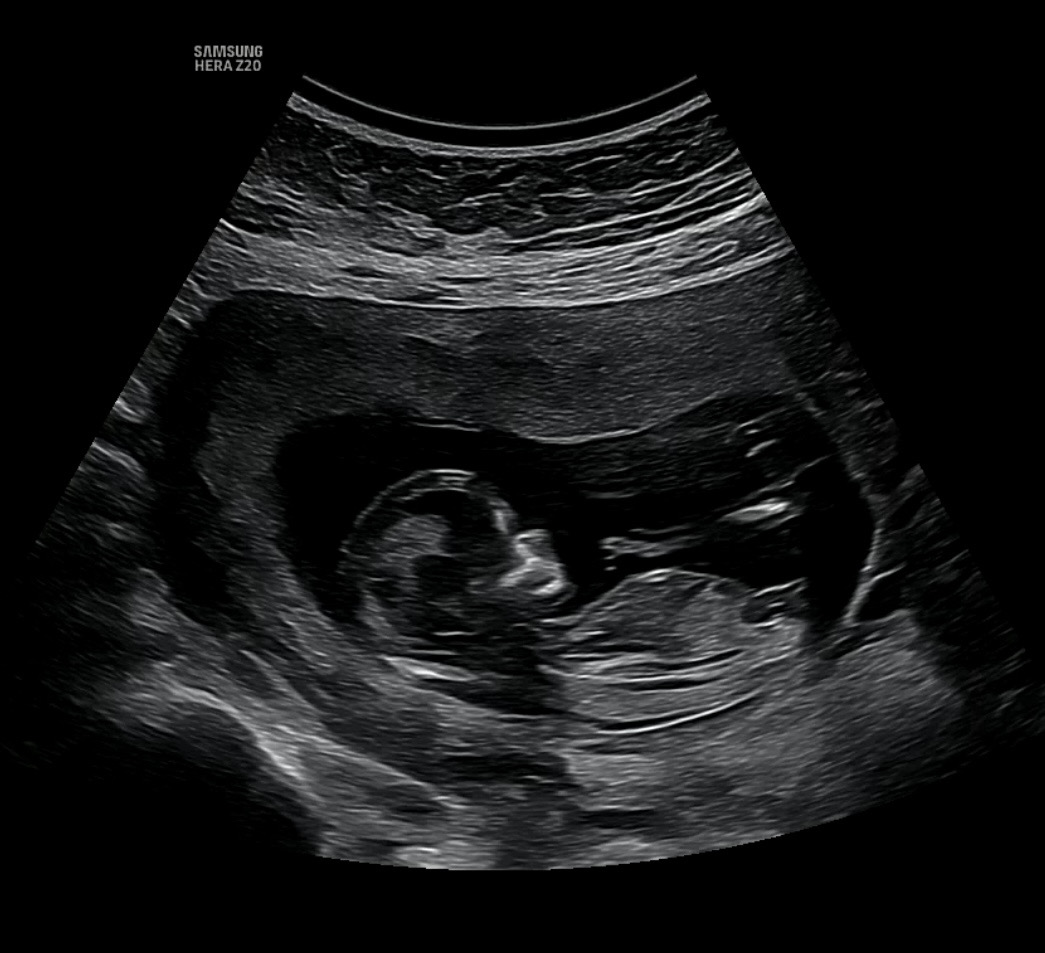

저도 각도법 봐주세요ㅎㅎ(12주 3일)

니프티 하긴 했는데 결과 나오기 전까지 너무 궁금하네요ㅜㅜㅎㅎ

딸인듯한느낌?

딸?